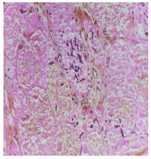

患儿2021年1月25日入院后完善相关检查临床诊断为急性淋巴细胞白血病(BCR/ABL融合基因阳性,BCR/ABL1p190阳性)。2021年1月27日给予VDLP(长春新碱+柔红霉素+左旋门冬酰胺酶+泼尼松)诱导化疗。7月29日患儿出现化疗后持续高热,热峰39.5°C,鼻皮肤黏膜破损,完善血mNGS检测检出德式根霉菌,给予静滴美罗培南40 mg/kg、每8小时1次,静滴两性霉素B脱氧胆固醇硫酸脂4 mg/kg、每日1次,泊沙康唑0.5 ml/(kg·d),分2次口服治疗。10月30日患儿出现鼻塞,流涕症状,体格检查双侧鼻腔黄脓性痂皮及干酪样黑色坏死物,口腔上腭沿正中线方向可见一条形褐色溃疡面,范围约1.5 cm×0.5 cm。完善鼻窦CT检查示双侧鼻腔内异常密度影,双侧上颌窦、筛窦、蝶窦及额窦黏膜不均匀增厚,软硬腭交界区不规则透亮影,局部软组织缺失。鼻内镜检查见双侧鼻腔较多干脓血痂附着,鼻腔分泌物真菌涂片检出根霉菌(图3)。12月2日全麻手术清理痂皮及坏死物,见鼻中隔部分骨质坏死,鼻中隔穿孔,穿孔大小约3.0 cm×3.0 cm,前至下鼻甲前端水平,后至后鼻孔水平,上至上鼻甲下缘水平,下至鼻底。清理物留送病理示毛霉菌感染(图4),继续两性霉素B脱氧胆固醇硫酸脂4 mg/kg、每日1次抗真菌治疗。

诊断毛霉菌病的金标准是组织病理学检查和真菌培养,临床为了早期诊断,正在尝试聚合酶链反应(PCR)、基质辅助激光解吸/电离飞行时间质谱(MALDITOF)和血宏基因组学第二代测序(mNGS)等[6]。鼻脑型毛霉菌病可累及颅内组织及神经,但并不宜行脑脊液分析诊断[7]。本例患儿行血mNGS检查提示根霉菌,进一步组织病理学及真菌涂片明确诊断为根霉菌。CT、MRI等影像学检查可提示病变部位、范围及骨质破坏情况。组织标本内见大量较粗、无分隔、孢芽垂直样分出的菌丝是确诊毛霉菌病的"金标准",另可见出血性梗死、凝固性坏死、血管血栓形成、中性粒细胞浸润和侵犯神经结构等相对特征性改变[8]。国外报道局灶性慢性鼻脑型毛霉病组织病理多表现为以多核巨细胞为主的慢性肉芽肿性改变,菌丝或孢子结构周围可见高度嗜酸性物质沉积,又称之为Splendore-Hoeppli现象[9]。